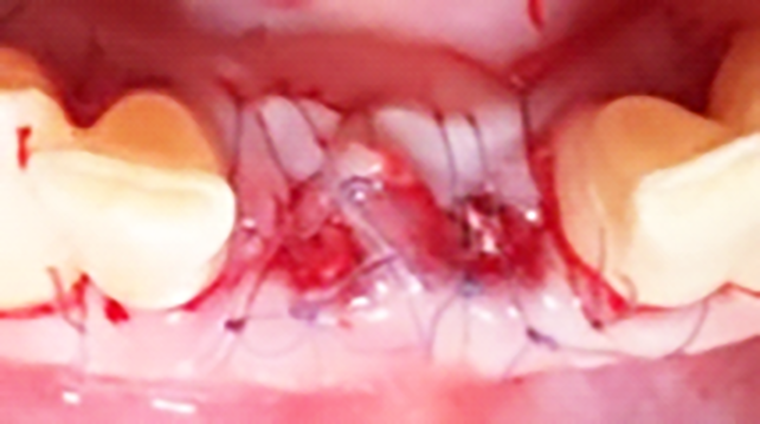

Dopo 10 mesi, si esegue di un lembo con incisione intrasulculare per gli elementi adiacenti alla sella edentula e festonata sulla sella edentula stessa.

Il lembo viene sollevato a spessore totale sia vestibolarmente che palatalmente (figura 7).

Si effettua la chirurgia implanto protesica guidata con mascherina (figura 8), si posizionano gli impianti 3.25 x 13 mm con un torque di 25 N (figura 9), si inseriscono i pilastri definitivi e si sutura (figura 10). Lo stesso giorno vengono ribasati e consegnati i provvisori solidarizzandoli con composito agli elementi 32-42 (figura 11).